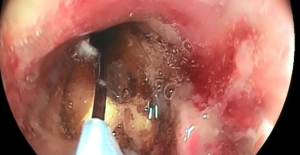

Akduman’ın suyla birlikte içtiği yarım cevizin sol akciğerine kaçtığı saptandı. ceviz, yapılan operasyon sonucunda akciğerden çıkarıldı. akduman, aynı gün taburcu edilerek evine gönderildi. cevizin çıkarıldığı operasyon ise kamera yardımıyla kayıt altına alındı.

Göğüs hastalıkları uzmanı arzu ertem cengiz de hasta nefes darlığı şikayetiyle başvurduğunu belirterek, şu ifadeleri kullandı: ‘koronavirüs açısından değerlendirmelerimizi yaptık ama herhangi bir bulguya rastlayamadık. hastanın hikayesini derinleştirince, suyun içine koyduğu cevizin akciğere kaçabileceğini düşündük ve bronkoskopi işlemi yaptık. sol akciğeri tıkayan cevizi gördük. uygun ekipmanlarla cevizi çıkararak hastayı rahatlattık. sonrasında hasta iki gün kadar antibiyotik tedavisi aldı. belirgin olarak rahatladı. hasta iyi bir şekilde taburcu edilerek evine gönderildi.’

Gerçekleştirdiği operasyon sonucunda cevizi tek parça halinde akciğerden çıkardığını söyleyen gastroenteroloji uzmanı irfan uruç, ‘endoskopik olarak mideden çeşitli şeyler çıkarıyorduk ama akciğerde böylesine ilginç bir şey çıkarmak bizler için ilk oldu. yabancı cismi görünce oradan çıkarmamız gerekiyor. bırakma şansımız yok.

Normalde mide balonu çıkarırken kullandığımız kancalı malzemenin bu hasta için uygun olabileceğini düşündük. kıskaç gibi tutarak cevizi tam parça halinde dışarıya alma imkanımız oldu. ekip olarak çok mutlu olduk. bunu yapamamış olsak belki hastanın hayatına mal olabilirdi. hep birlikte böyle bir iş çıkardık. mutluyuz, hastamız adına da sevinçliyiz’ diye konuştu.